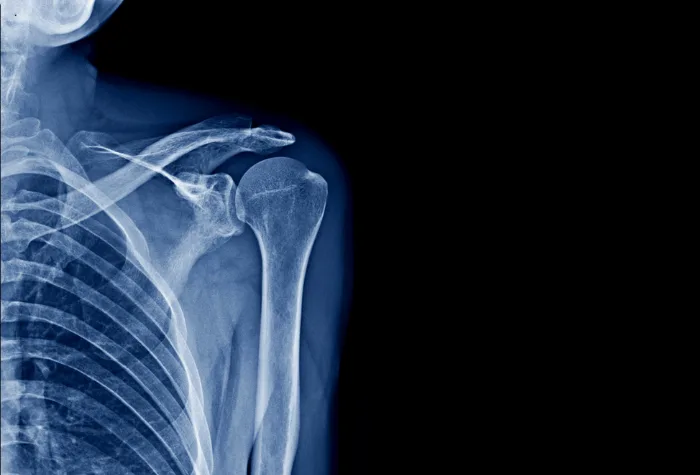

Thumbnail image courtesy: angkhan/ Getty Images Pro.